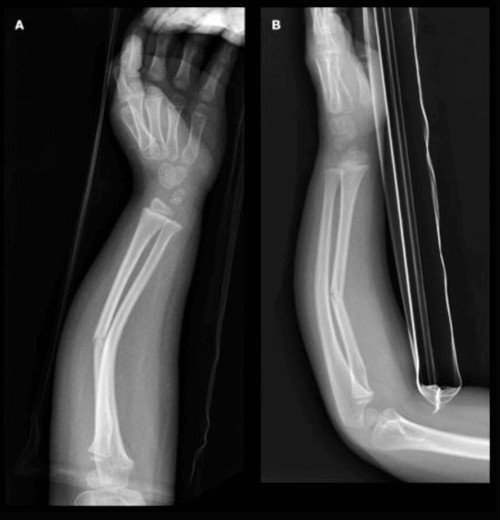

Greenstick fracture of wrist is actually the fracture in the lower third or middle third of radius or ulna (the bones in forearm). This happens when a child falls flat on the floor with outstretched arm or impact to the palm while falling from height. Direct blow to the forearm may result in the greenstick fracture of upper and middle third of radius or ulna. [4,5]

Fig 4: Greenstick fracture radius and ulna